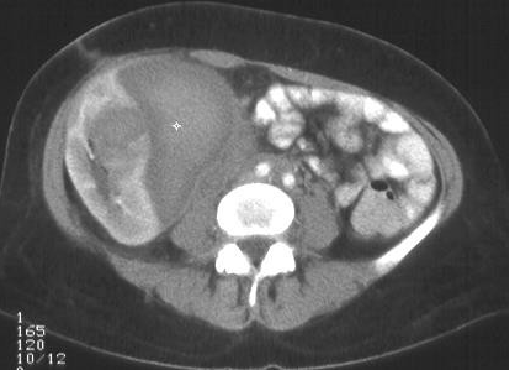

肾活检穿刺有时会伤及肾外动脉导致致命出血 年轻女性,急性肾功能衰竭(goodpasture syndrome),需要紧急活检。共穿刺5次。超声探及肾周血肿,血压下降需要输血。紧急血管造影